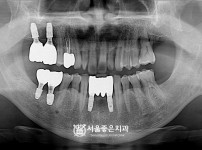

|  | 338 |  | 뼈이식 수면임플란트 10개 - 네오 임플란트 / 의치 쓰시다가 불편해서 임플란트 하심